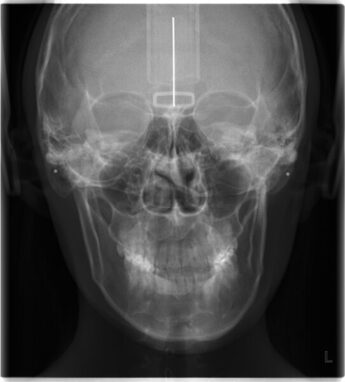

- 口腔内レントゲン撮影による骨格分析

なぜレントゲン診断が必要なのか

皮膚の上から見える顔は「結果」であり、原因は骨格内部に存在します。

レントゲン分析により、

- 顎の位置

- 骨格傾斜

- 咬合状態

- 左右差

を客観的に確認できます。

顔ドックは日本で唯一、

医療連携のもと骨格確認後に矯正施術を開始する顔専門研究所です。